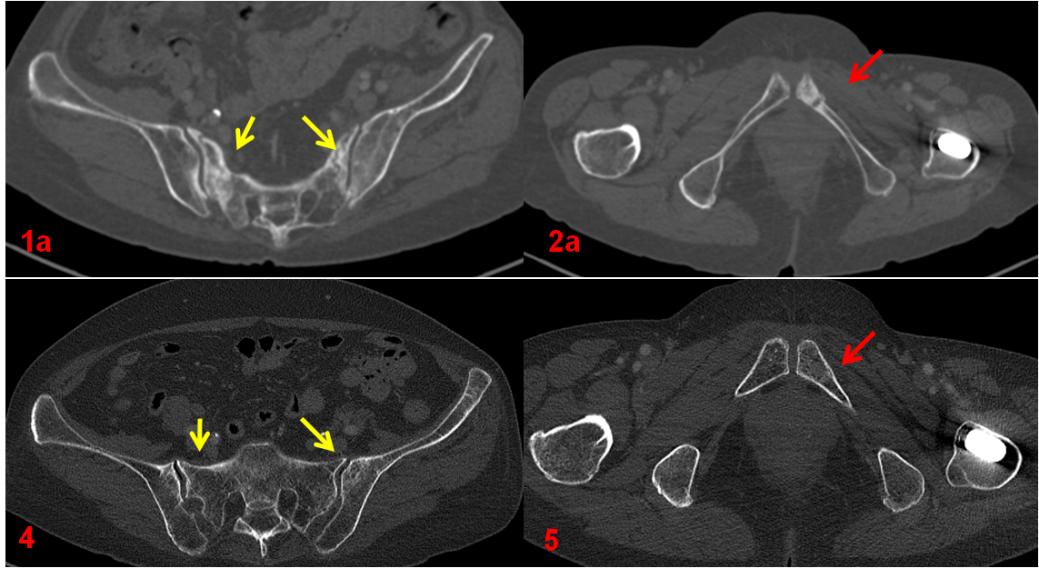

ECT全身骨顯像診斷為機(jī)能不全骨折,建議患者隨診復(fù)查。患者于1年后復(fù)查平掃CT及ECT全身骨顯像,綜合兩次影像學(xué)資料,考慮骨折修復(fù)愈合。

復(fù)查CT(圖4、5)對比前片(圖1a、2a)。前片所示骶骨密度不均勻增高(1a,黃箭),本次明顯恢復(fù)(4,黃箭),左側(cè)恥骨骨質(zhì)斷裂(2a,紅箭),本次基本消失(5,紅箭)。